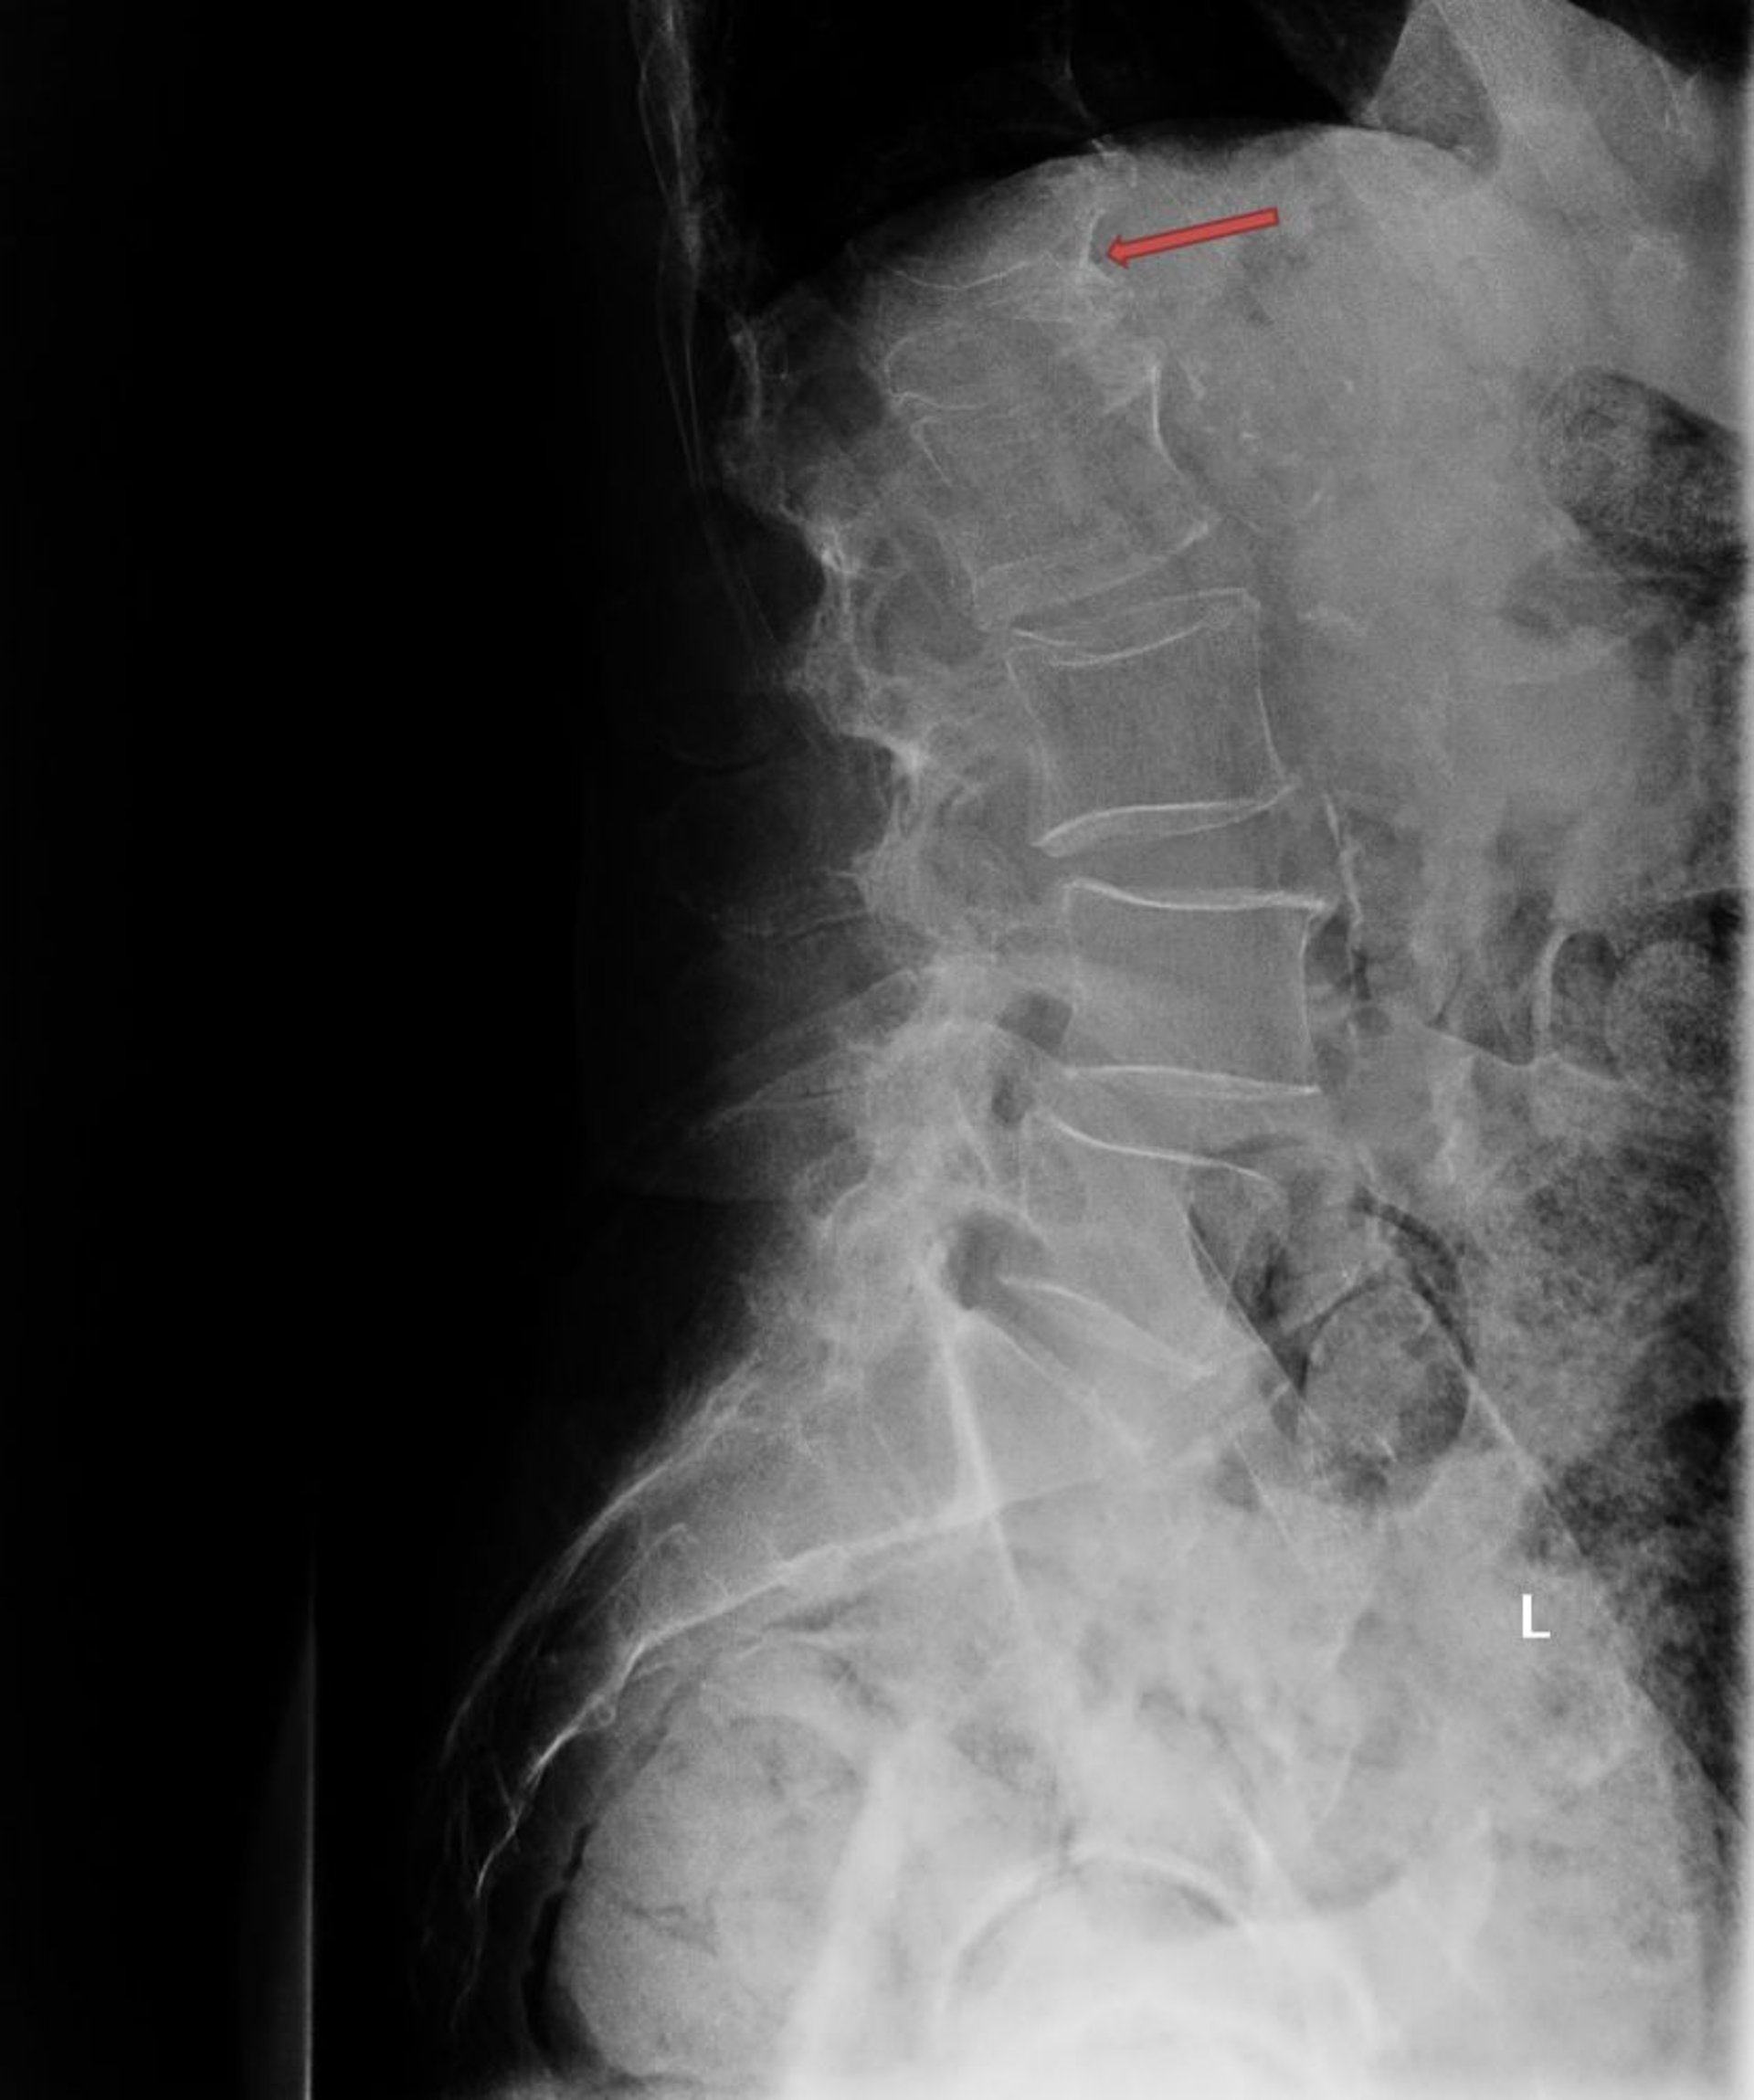

Diese Röntgenaufnahme zeigt eine schwere osteoporotische Kompressionsfraktur des ersten Lendenwirbels (L1; Pfeil).

Osteoporotische Kompressionsfraktur